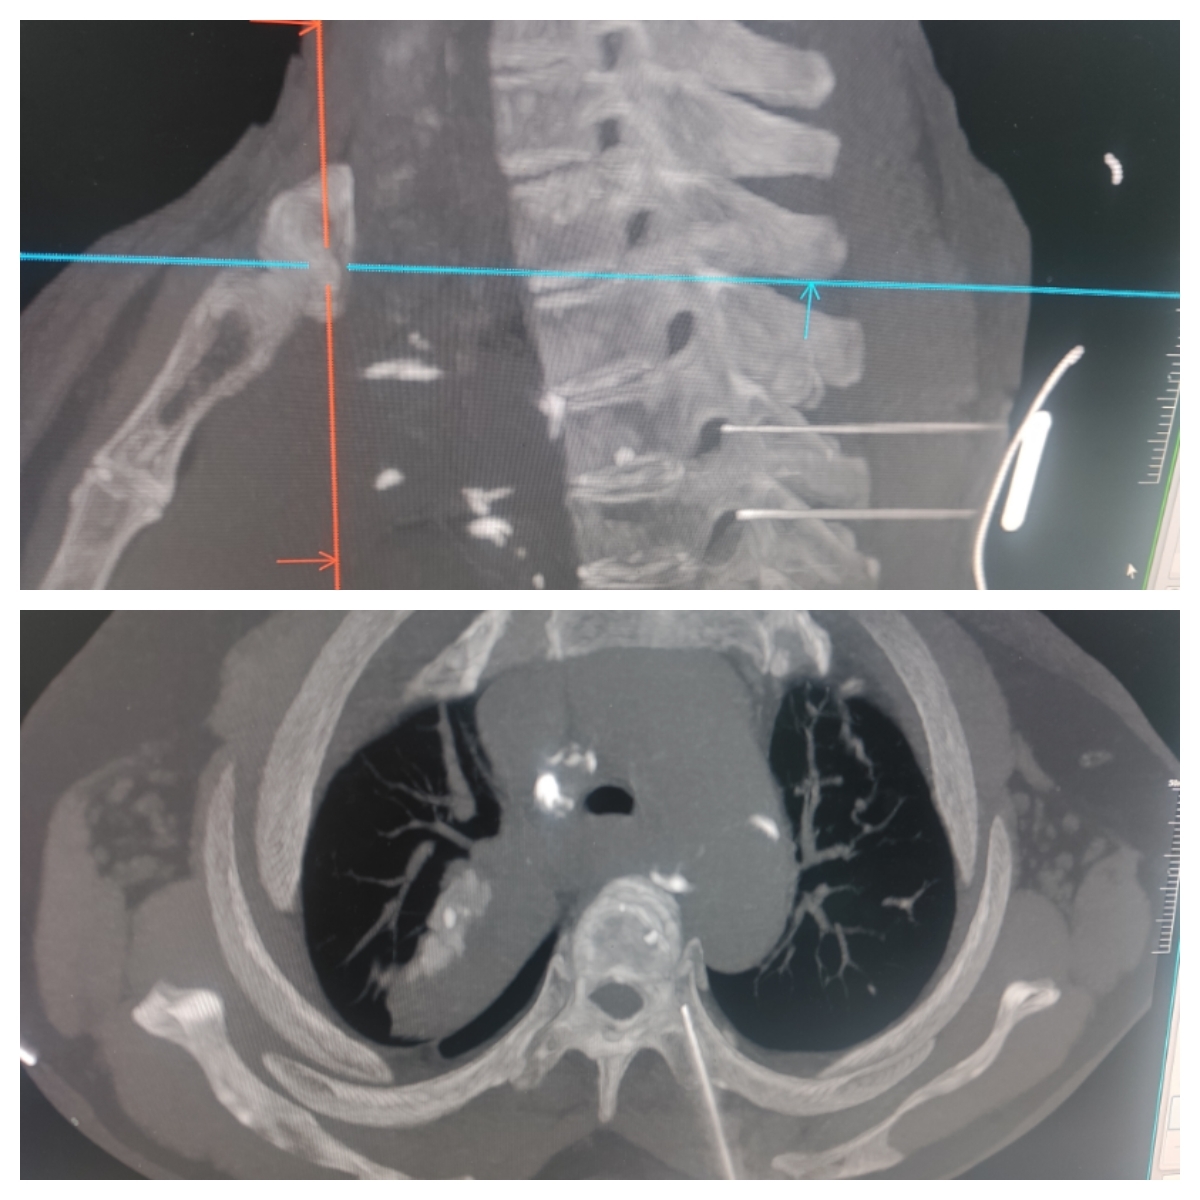

颈胸段神经治疗因解剖结构复杂、操作空间狭小、毗邻重要血管与脊髓,风险系数高,一直被业内视为外周神经治疗的技术“制高点”。

在宁波“组团式”医疗帮扶队队长、越西县人民医院院长曹刚主任医师的带领与指导下,医院疼痛科团队成功掌握了这一高难度技术。治疗中,医生在影像设备的精确引导下,将治疗精准作用于目标神经根,实现了“毫米级”的精准操作,有效避免了周围重要组织的损伤。